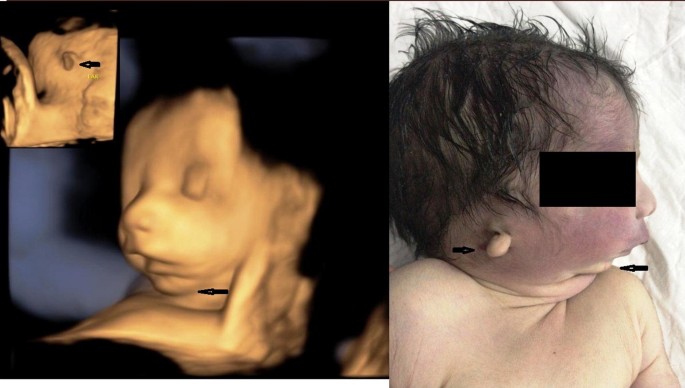

Treacher Collins Syndrome Role Of 3d 4d Ultrasound In The Assessment Of Fetal Facial Dysmorphism Html